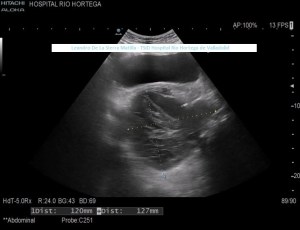

Durante el estudio del peritoneo, retroperitoneo y cadenas linfáticas abdominales, observamos una lesión superficial, redondeada, heterogénea, hipo-Isoecogénica con zonas hiperecogenicas, de aspecto sólido.(FIGURA 4)

4

Cambiamos a una sonda lineal para un estudio más detallado, observando una LOE hipoecogénica con zonas híper-isoecogénicas, heterogénea, sólida, sin contenido de asas intestinales ni de grasa, con bordes mal definidos y con flujo doppler en su interior, ubicada dentro de la cavidad umbilical (FIGURAS 5, 6 Y 7)